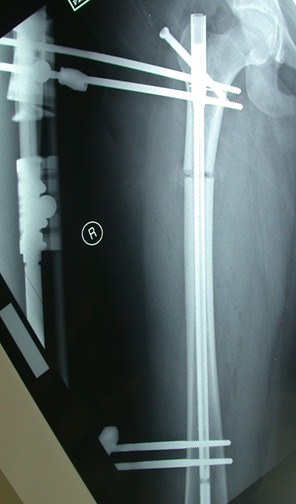

التطويل باستخدام المسامير النخاعية الداخلية ذاتية التطويل

يعتبر مركز البروفيسور الصياد من رواد جراحة تطويل العظام التجميلية وتطويل العظام بالمسامير الداخلية ذاتية التطويل. وقد بدأت عمليات التطويل الخاصه بنا في شهر يونيو 2002م

وبدأ استخدام  تقنية المسمار النخاعي  من عام 2008م  أي  قبل استخدام هذه التقنية في الولايات المتحدة الامريكية بثلاث سنوات

وقد كان الاستخدام الاولي بجهاز الفت بون الالماني الرائد وقد تم عمل مئات العمليات بهذه التقنية, اضافة الى

استخدام مسمار البريسايز2 المتميز وكلاهما يعمل بالريموت كنترول ,

بالنسبة للفت بون يعمل بمجال الكهربائي الداخلي وموتور داخلي  بالمسمار, والبريسايز 2 يعمل باستخدام تقنية مغناطيس كبير الحجم خارجي في وحدة تدعى(ERC) لتحريك مغناطيس داخل المسمار يؤدي لتطويل المسمار عن طريق هذا التفاعل المغناطيسي.

ويستخدم في تعويض الطول في عظمة الساق والفخذ والعضد.